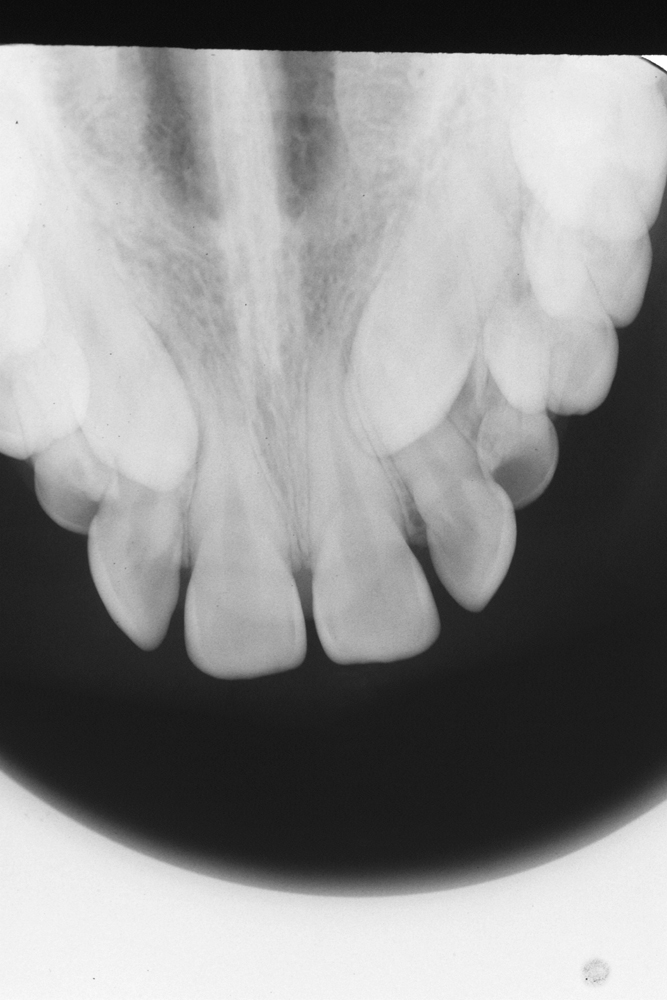

Intraoral radiographs are taken as needed, there are various such views (on intraoral films). The upper anterior occlusal radiograph is the most commonly used. This view uses an imaginary plane to focus on the maxilla and upper front teeth. It is essential for the assessment of unerupted canine teeth. Figure 10 shows an example of an upper anterior occlusal radiograph.

Figure 10: Upper anterior occlusal image, allowing localisation of ectopic canine teeth.